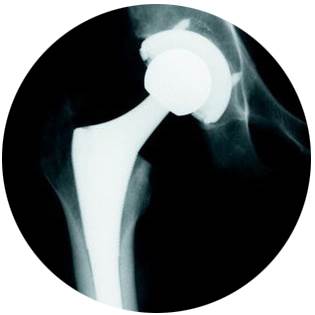

The leading cause of hip pain is osteoarthritis, which is degenerative, meaning it won’t improve and may actually worsen. Early diagnosis and treatment of osteoarthritis are important. Hip replacement is a surgical procedure that removes and replaces diseased joint surfaces with implants. The surgery helps to relieve pain and improve mobility. During surgery, the diseased area in the hip socket is removed and replaced. A new cup is secured in the socket, a liner is placed within the cup, a stem is inserted into the leg bone (femur) and a ball is placed in the cup. The bearing, or union of the ball and cup, is another important element, and it comes in many different options, including metal, polyethylene (plastic), ceramic and combinations of those. Your surgeon will help determine the best bearing for you.

One of the total hip replacement surgical approaches we use is the anterior approach, which involves an incision made on the front (anterior) of the hip. The anterior approach differs from the traditional approach to hip replacement, which has patients lie on their side for the posterior or anterior lateral approach. First performed in 1947 by Robert Judet in France, it was adopted in 2002 by Dr. Joel Matta in California who modernized it and began to teach the technique in the United States.